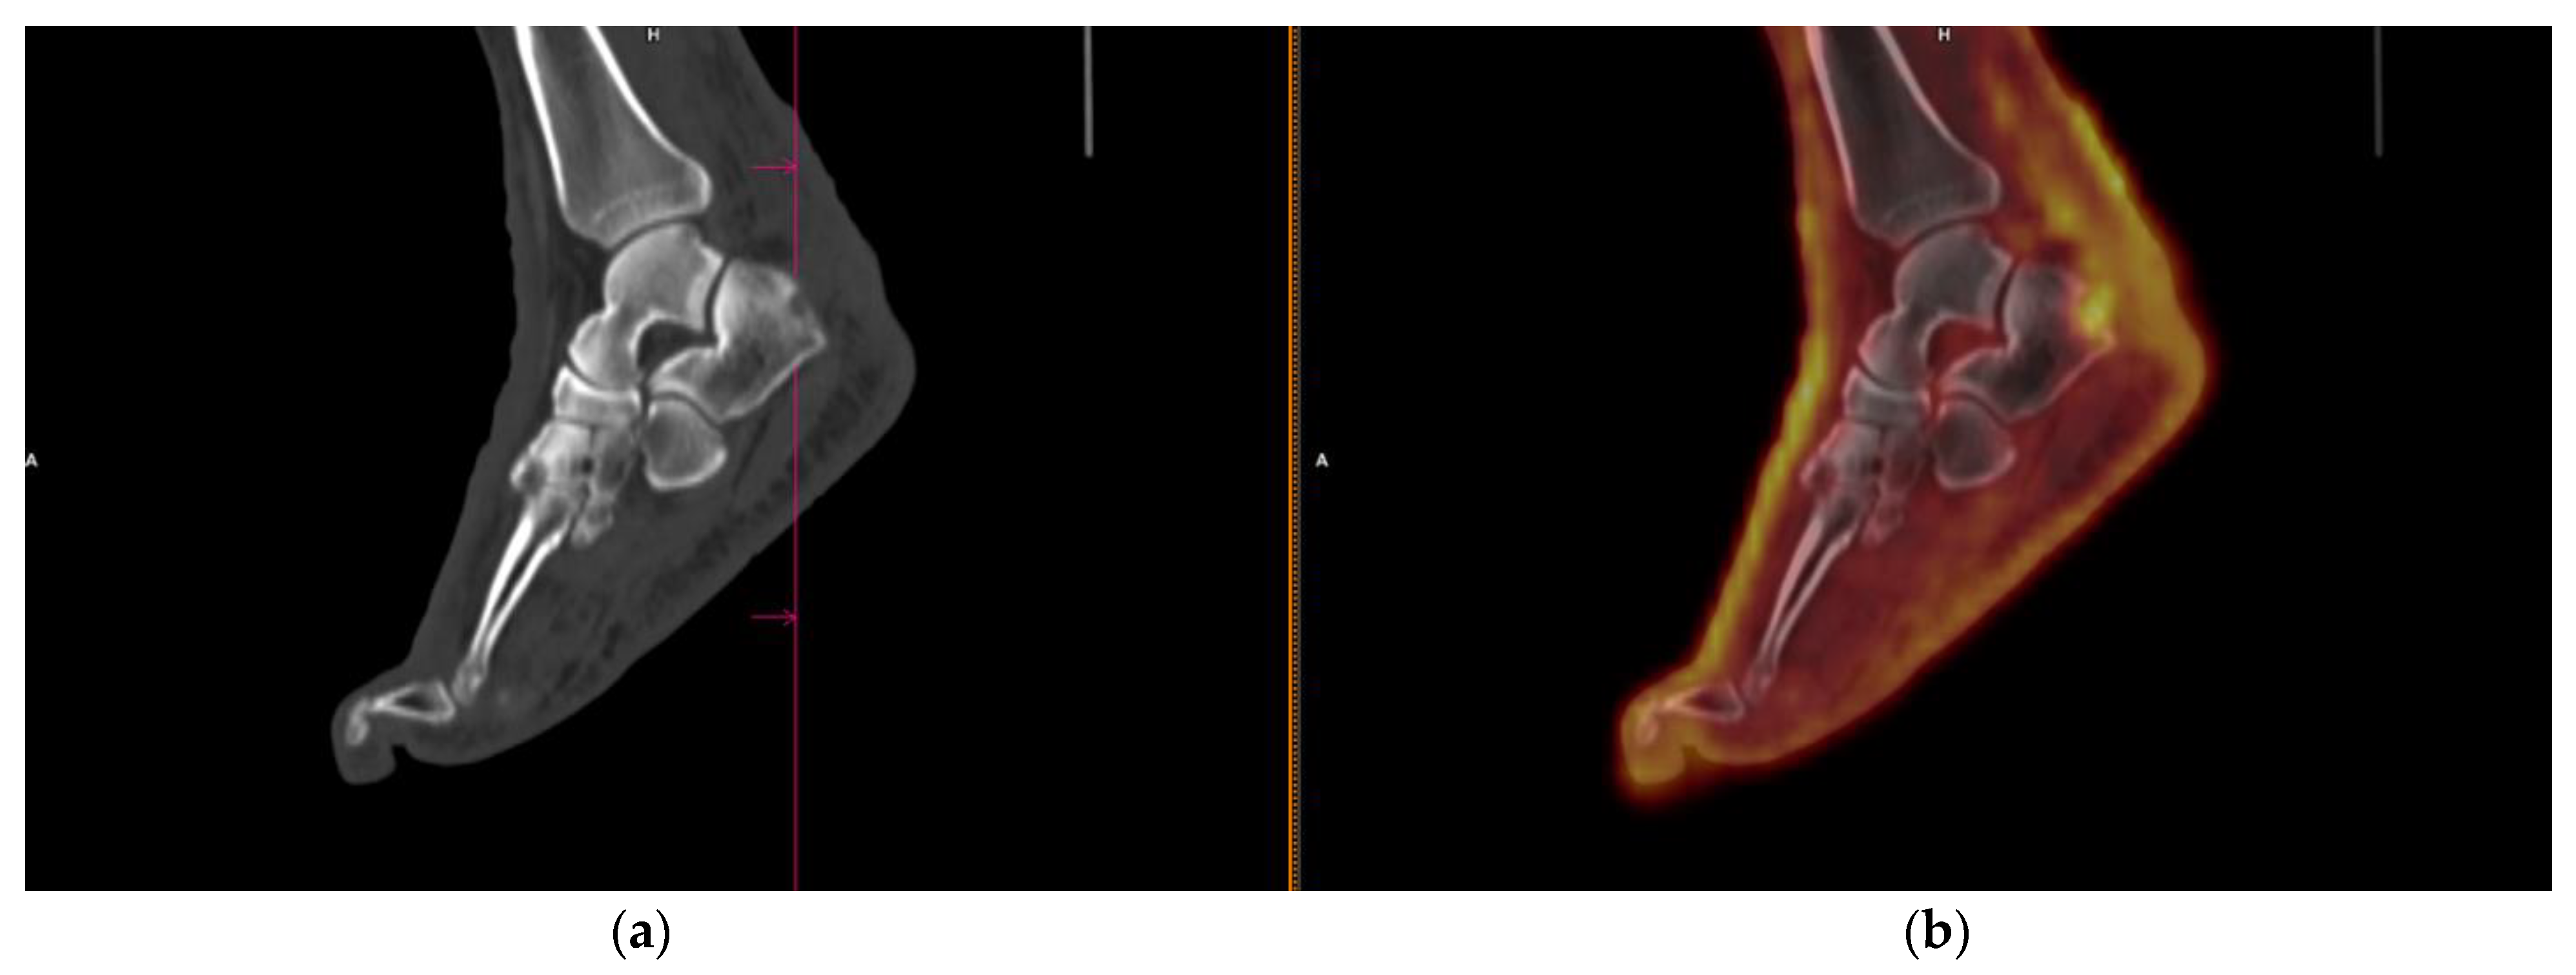

3.5. DA of FDG PET/CT for Cutaneous Lesions

| Bone | 13 | 1 | 59 | 2 | 87% | 98% | 80% | 97% | 96% |

| Muscle | 4 | 0 | 71 | 0 | 100% | 100% | 100% | 100% | 100% |